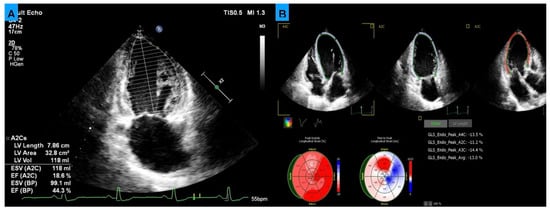

Prospective Study on the Evaluation of Echocardiographic Parameters as Predictors of a Positive Response to Cardiac Resynchronization Therapy in a Tertiary Care Hospital in Mexico

by Juan Carlos Plata-Corona, Karla Sofia Chávez-Gómez, Enrique Torres-Rasgado, Heberto Aquino-Bruno, José Omar Arenas-Díaz, Elias Terrazas-Cervantes and Nilda Espinola-Zavaleta

J. Clin. Med. 2026, 15(2), 609; https://doi.org/10.3390/jcm15020609 - 12 Jan 2026

Background/Objectives: Heart failure is a major global health problem. Among the available treatment options, cardiac resynchronization therapy (CRT) has been shown to improve both quality of life (QoL) and mortality; however, not all patients respond adequately. Our study aimed to identify echocardiographic parameters that predict a positive response to CRT. Methods: A total of 33 patients (10 women and 23 men) were prospectively recruited, all met the standard criteria for CRT implantation. Biochemical, clinical, QoL, 6 min walk test, and echocardiographic evaluations were performed prior to CRT implantation and reassessed after 6 months. A ≥15% reduction in left ventricular end-systolic volume was taken as the defining parameter of positive response. Based on response level, patients were divided into two groups: responders and non-responders. Results: Comparing the overall population before and after CRT, a positive impact was observed on biochemical, electrocardiographic, and echocardiographic parameters. Fourteen patients (42%) were classified as responders and nineteen (58%) as non-responders. Only two basal echocardiographic parameters showed significant baseline differences between groups: Global Longitudinal Strain (GLS) and the Kapetanakis index. ROC curve analysis showed that baseline GLS and Kapetanakis index had excellent discriminative ability for predicting CRT response. Also, binary logistic regression analysis identified the association of GLS and Kapetanakis index with CRT response. Finally, Rho Spearman analysis showed a positive correlation between the degree of response to CRT and the QoL, (ρ) of 0.663 with p = 0.001. Conclusions: Our findings confirm the overall clinical, biochemical, echocardiographic, and QoL benefits of CRT. In addition, two echocardiographic parameters proved to be potential response predictors. Full article